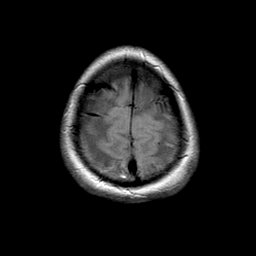

MR Study #1 -- Slice #22

[Home][Help][Clinical][Tour 1] Slice 22